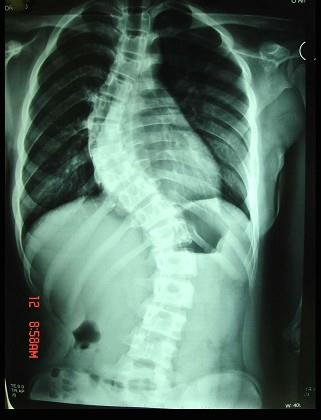

问题 脊柱侧凸(如图)的临床表现错误的是 ( )

选项 A、侧凸严重时,可引起心悸、气急 B、10岁以后畸形发展快 C、多发生在女性 D、18~20岁后侧凸进入稳定期 E、多发生在儿童和青少年

答案 D